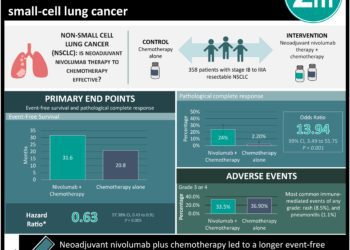

#VisualAbstract: Neoadjuvant nivolumab plus chemotherapy increases event-free survival in resectable non-small-cell lung cancer

1. Neoadjuvant nivolumab plus chemotherapy led to a longer event-free survival and higher percentage of patients with a pathological complete ...